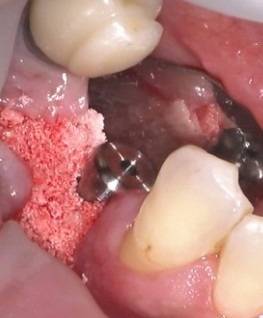

インプラント埋入手術+GBR(骨造成術)

術中

インプラント埋入手術では、局所麻酔・歯肉の切開・インプラント床の形成・埋入・縫合などを行いますがこれは一連の流れであり、途中でやめることはあまりありません。